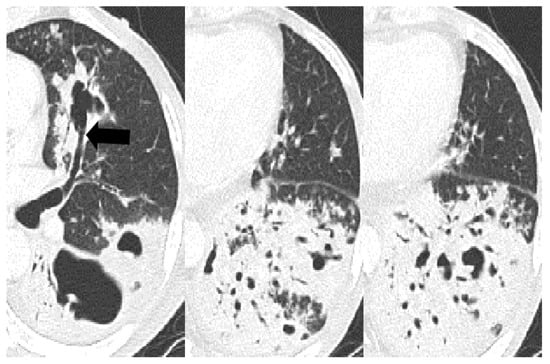

4. Discussion